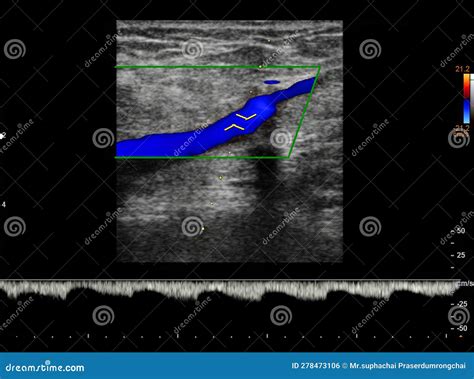

• Color Doppler Ultrasound: Uses color mapping to show the velocity and direction of blood flow, identifying areas where blood flow is restricted or absent due to an obstruction.

During the examination, the technician employs a technique called compression ultrasonography. By applying gentle pressure with the ultrasound probe, the examiner assesses whether the vein collapses. A healthy, patent vein will collapse completely under pressure, whereas a vein containing a thrombus will remain rigid and fail to compress, serving as a primary diagnostic indicator of a clot.